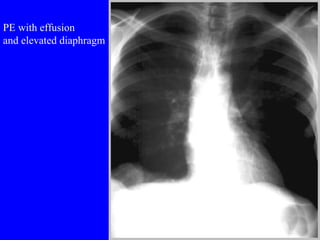

Pulmonary embolism (PE) is a common and potentially fatal condition where blood clots block arteries in the lungs. An estimated 5 million venous thromboses occur annually worldwide, with 10-30% of PE cases correctly diagnosed. Risk factors include older age, cancer, obesity, surgery, trauma, and genetic or acquired hypercoagulable states. Diagnosis involves assessing clinical probability based on symptoms and risk factors, then confirming with tests like D-dimer, chest imaging, ventilation-perfusion scanning, pulmonary angiography, or CT pulmonary angiography. Treatment focuses on anticoagulation to prevent further clotting while allowing natural lysis of existing thrombi.